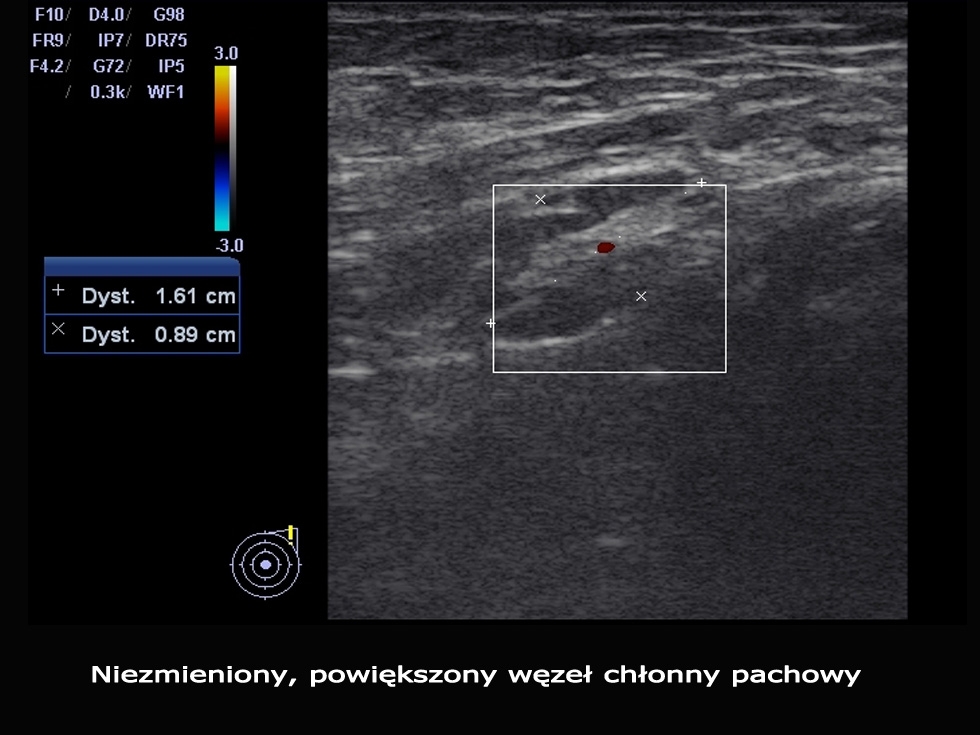

Badanie USG jest podstawową metodą oceny wielkości oraz budowy węzłów chłonnych. Pozwala z dużą dokładnością ocenić czy badany węzeł chłonny ma podejrzany charakter i czy wymaga pilnej diagnostyki inwazyjnej (np. biopsji). W badaniu tym ocenia się również charakter unaczynienia węzłów (w technice Power-Doppler), gdyż unaczynienie to w różnych schorzeniach ulega poważnym zaburzeniom (dotyczy to głównie węzłów zajętych przez nowotwór).